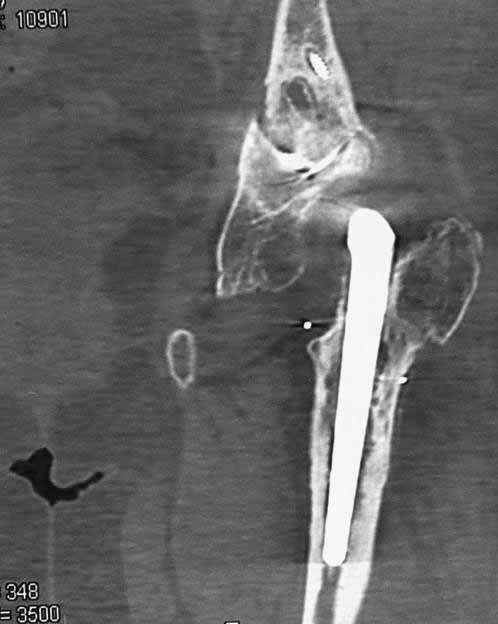

Уважаемые коллеги. Хотелось бы услышать мнения и советы по представляемому случаю. Пациентка 45 лет. Бесцементное эндопротезирование левого тазобедренного сустава 6 лет назад (впадина RM, Mathys, металл-металл, ножка Зульцеровская). За 10 лет до протезирования – коррегирующая остеотомия бедренной кости, которая не срослась в течение года до удаления пластины, а затем срослась в течение 3 месяцев иммобилизации в кокситной повязке. После протезирования получилось наблюдать пациентку почти постоянно, поскольку через 2 года синтезировал ей лодыжки на оперированной стороне, затем, через несколько месяцев удалил фиксаторы, а в 2009г. резецировал мениск на противоположной стороне. Боли все эти годы не беспокоили. Пациентка чуть выше среднего роста, вес тела нормальный. Физические нагрузки переносила хорошо. Работает на 7 этаже без лифта. Год назад экстирпация матки по поводу лейомиомы больших размеров. Несколько месяцев назад появились боли в области левого тазобедренного сустава. При рентгеновском и КТ исследованиях (июль с.г.) – нестабильность тазового компонента. От предложенной замены протеза пациентка на тот момент, слава богу, отказалась. Через какое то время боли в области левого тазобедренного сустава практически полностью прошли, а около 2 месяцев назад появилось ощущение патологической подвижности таза и боли в паху справа, которые через некоторое время уменьшились, а потом снова усилились после значительных физических нагрузок (много ходила по песку на пляже, носила тяжести). Ежедневно принимала диклофенак. На рентгенограммах – переломы правой лонной кости. Сейчас госпитализирована из-за болей в паху справа. Боли слева не беспокоят. На фоне снижения нагрузок в стационаре боли значимо уменьшились. Способна ходить без средств дополнительной опоры.В анализах крови чуть повышены трансаминазы и гамма-ГТ, моча без особенностей.

Вопросы: -правильно ли я расцениваю переломы как стрессовые на фоне неполноценного таза (pelvic insufficiency stress fractures)? -Можно ли так же расценить ситуацию на стороне протеза и, соответственно, не торопиться с ревизией, рассчитывая на вторичную стабилизацию? Уж больно не хочется менять ножку. -Если думать о ревизии, то когда? На представленных снимках тазобедренный сустав до и сразу после операции, затем 2 снимка 2009г., когда ничего не беспокоило, затем КТ 2-х месячной давности и вчерашние рентгенограммы обоих тазобедренных суставов.